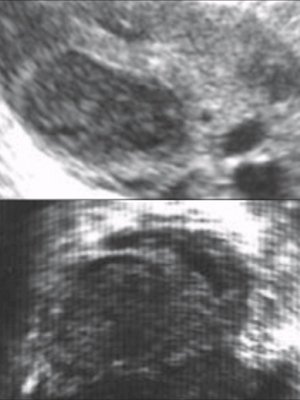

Отсутствие секреторных изменений в эндометрии характеризовалось сохранением его трехслойного строения, типичного для предовуляторного периода, с гипоэхогенными функциональными слоями (рис. 2). Данная эхографическая картина эндометрия наблюдалась у 12% пациенток с НЛФ и обусловлена, вероятно, не только снижением секреции прогестерона желтым телом яичников, но и нарушением на уровне рецепторного аппарата эндометрия. В контрольной группе у всех женщин эндометрий обладал повышенной эхогенностью, что свидетельствовало об адекватной секреторной трансформации (рис. 3).

Рис. 2. Отсутствие секреторных изменений в эндометрии.

Рис. 3. Состояние эндометрия в лютеиновую фазу физиологического менструального цикла.